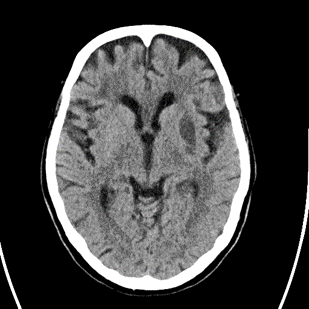

8/ Next evening, patient does the same thing, NIHSS=8, word-๐Ÿฅ—, worsening right hemiparesis. #Strokealert again and CT with new stroke noted. BP at this time 110s:

9/ CTA/P completed as well. LM1 thrombus now appears <occlusive (note that calcification makes vessel appear >open than it actually is), CTP without clear penumbra, but TMax high in posterior MCA division.